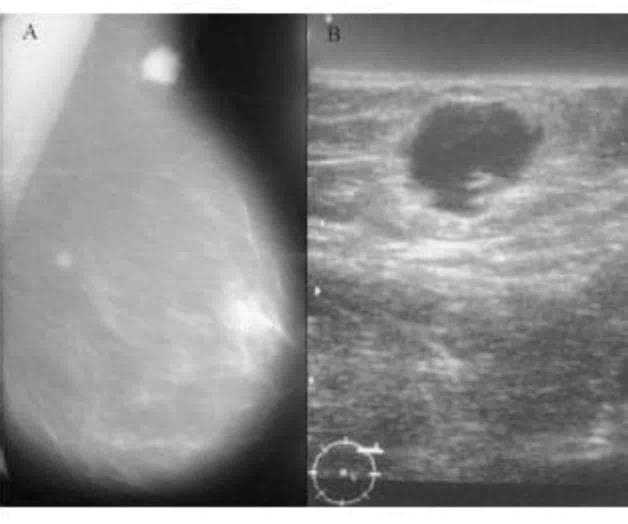

Destaca que algunas veces el cáncer de seno es detectado después de que surgen síntomas, pero existen muchos casos en no llegan a manifestar signo alguno, es por eso que hacer las pruebas de detección periódicas como autoexploración, ultrasonido y mamografía es tan importante.

El síntoma más común del cáncer de mama es una masa o bulto, si es dura y con bordes irregulares tiene más probabilidades de ser cáncer, pero también pueden ser sensibles a la palpación, blandos y de forma redondeada, en cuyo caso es importante que sean examinados por un profesional de la salud.

Conocer los signos a los que se debe prestar atención no reemplaza a los mamogramas ni a otras pruebas de detección, pues estas pueden ayudar a encontrar la enfermedad en sus comienzos, antes de que aparezca algún síntoma, lo cual da más probabilidades de que el tratamiento sea eficaz.